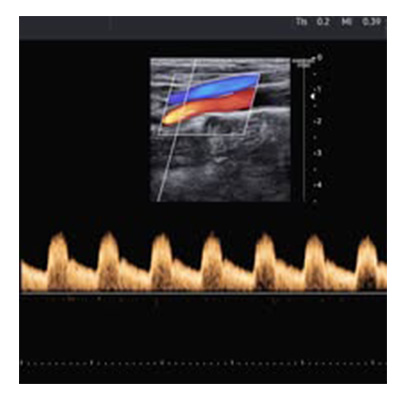

Il Dott. Andrea Velati è Medico Chirurgo e specialista in Angiologia Medica dal 1998. Con una solida esperienza, si occupa della diagnosi e del trattamento delle patologie vascolari, arteriose, venose e linfatiche, garantendo un approccio professionale e personalizzato per ogni paziente. Tra i servizi offerti rientrano l'Ecocolordoppler di tutti i distretti vascolari, comprese carotidi, arti inferiori e superiori, e aorta addominale. Diagnosi e trattamento delle patologie delle carotidi. Gestione di patologie arteriose e venose, come l'arteriopatia obliterante e la malattia venosa. Diagnosi e cura di linfedemi degli arti inferiori. Individuazione e monitoraggio di aneurismi dell'aorta addominale. Il Dott. Velati si impegna a offrire soluzioni efficaci e mirate per preservare la salute vascolare dei suoi pazienti, utilizzando tecnologie avanzate e un approccio centrato sulle esigenze individuali. Il Dott. Velati visita anche in Via Giuseppe Garibaldi, 3,  Sanluri, Via Gennargentu 7,  Oristano e Via Guido Cavalcanti 4,  Cagliari

Keywords varici, angiologia, ecocolordoppler, ecografie, visite specialistiche, chirurgia vascolare, ecodoppler, flebologi, oristano, sanluri, cagliari.